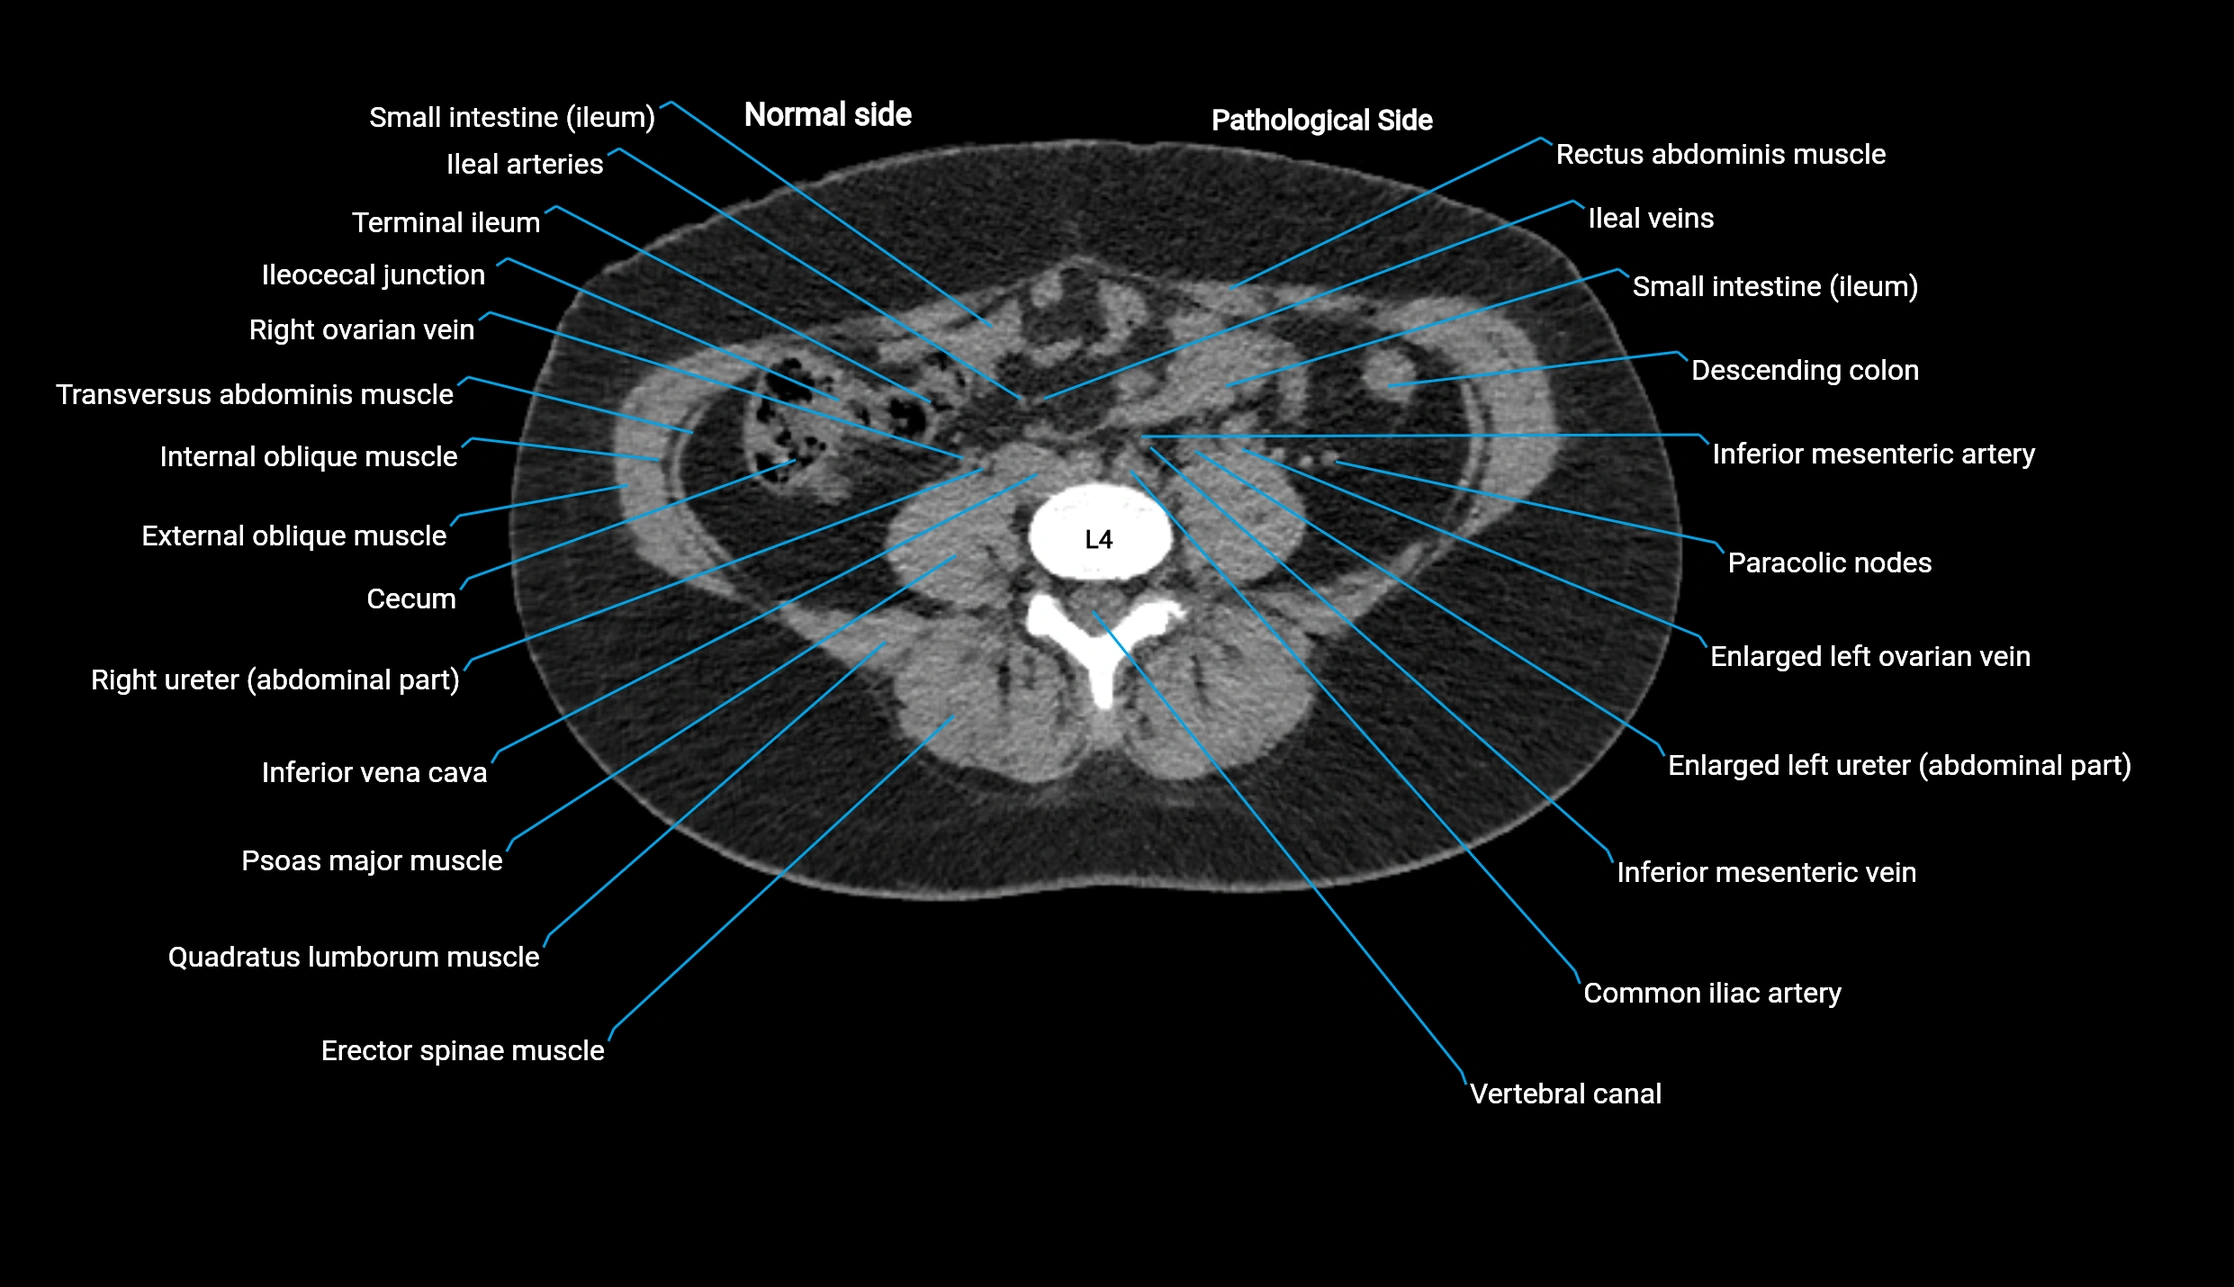

CT image

image